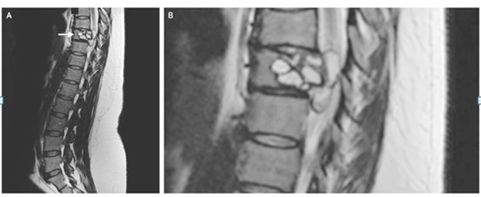

女子脊椎中发现寄生虫

Credit: The New England Journal of Medicine

一名法国妇女称其腿部会出现“电击”的感觉,经检查发现,她患有一种罕见的感染——脊椎里潜伏着绦虫幼虫。

这名女性背部的核磁共振显示,其脊柱有一处病变,需要手术切除。进一步的测试显示,这种病变是由细粒棘球绦虫感染引起的,这是一种小型绦虫,常见于狗和一些农场动物(绵羊、牛、山羊和猪等)。

这种绦虫可引起一种叫做包虫病的疾病,在这种疾病中,幼虫会形成囊肿,并在人体内缓慢生长。这种疾病在法国很少见,研究人员尚不清楚这位妇女是如何感染的。据报道,她曾接触过马和牛等农场动物。研究人员还怀疑,可能是吃了被寄生虫污染的蔬菜导致。在接受了一种抗寄生虫药9个月后,该妇女残留症状消失。

7月11日,《NEJM》杂志发表了该病例的报告。